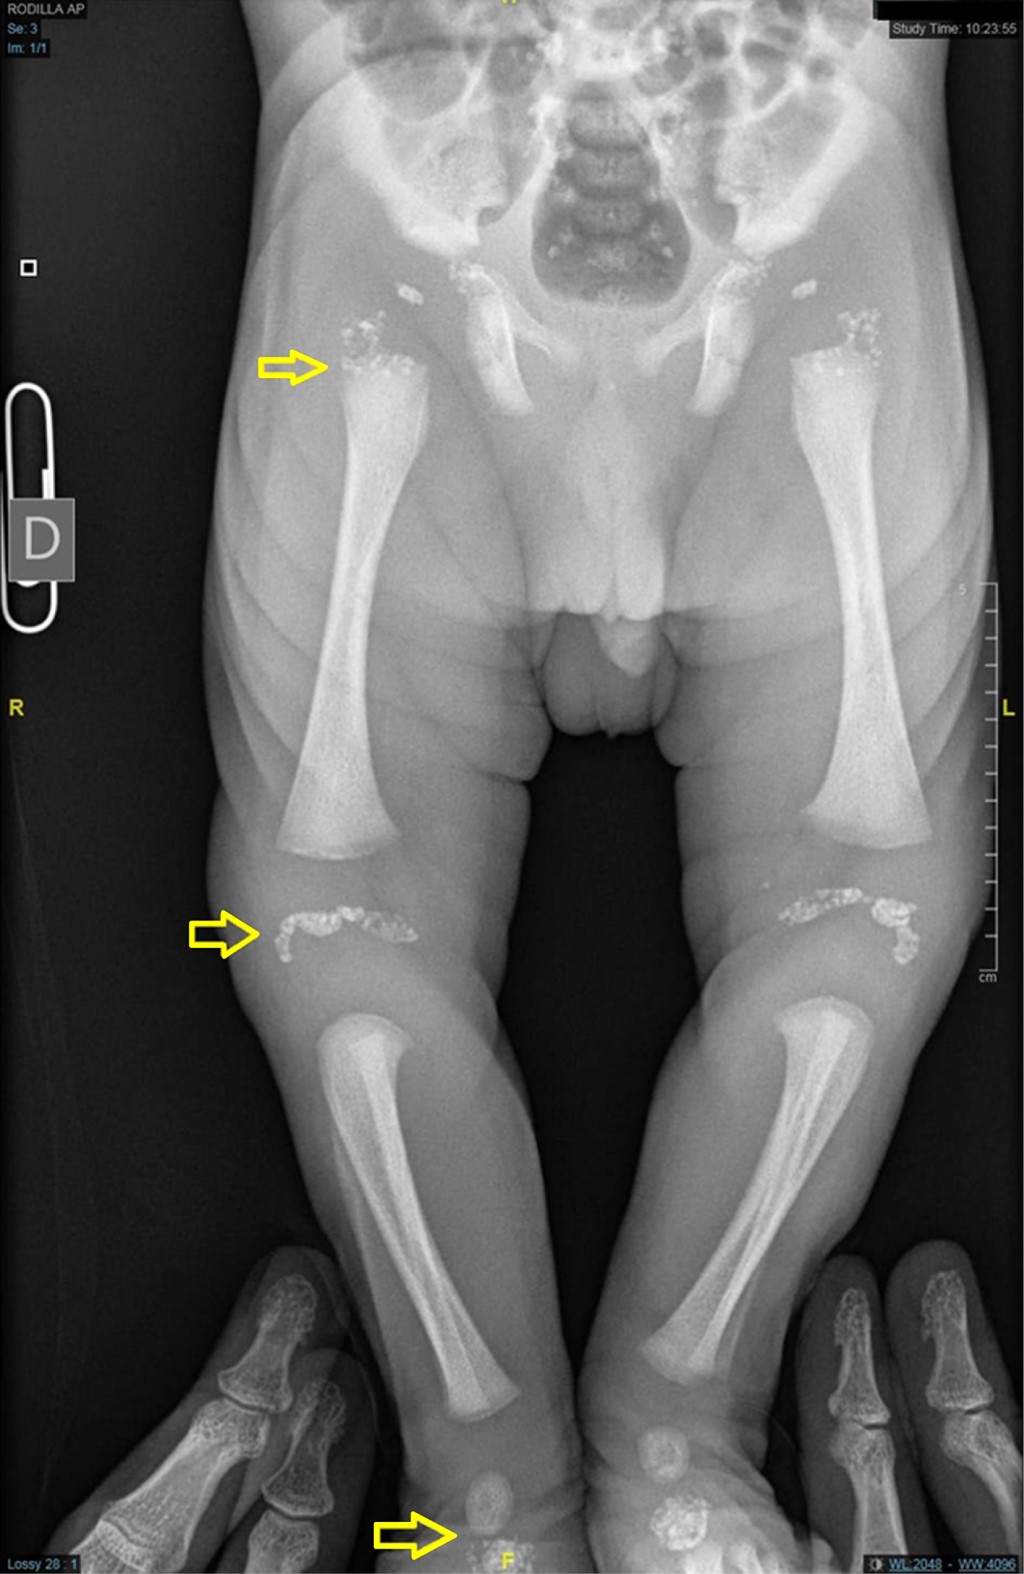

Chondrodysplasia punctata in neonate

We present the radiographic images of a newborn in whom a diagnosis of chondrodysplasia punctata was reached. Patients with this disorder have pinpoint calcifications in multiple joints.

Figure 3